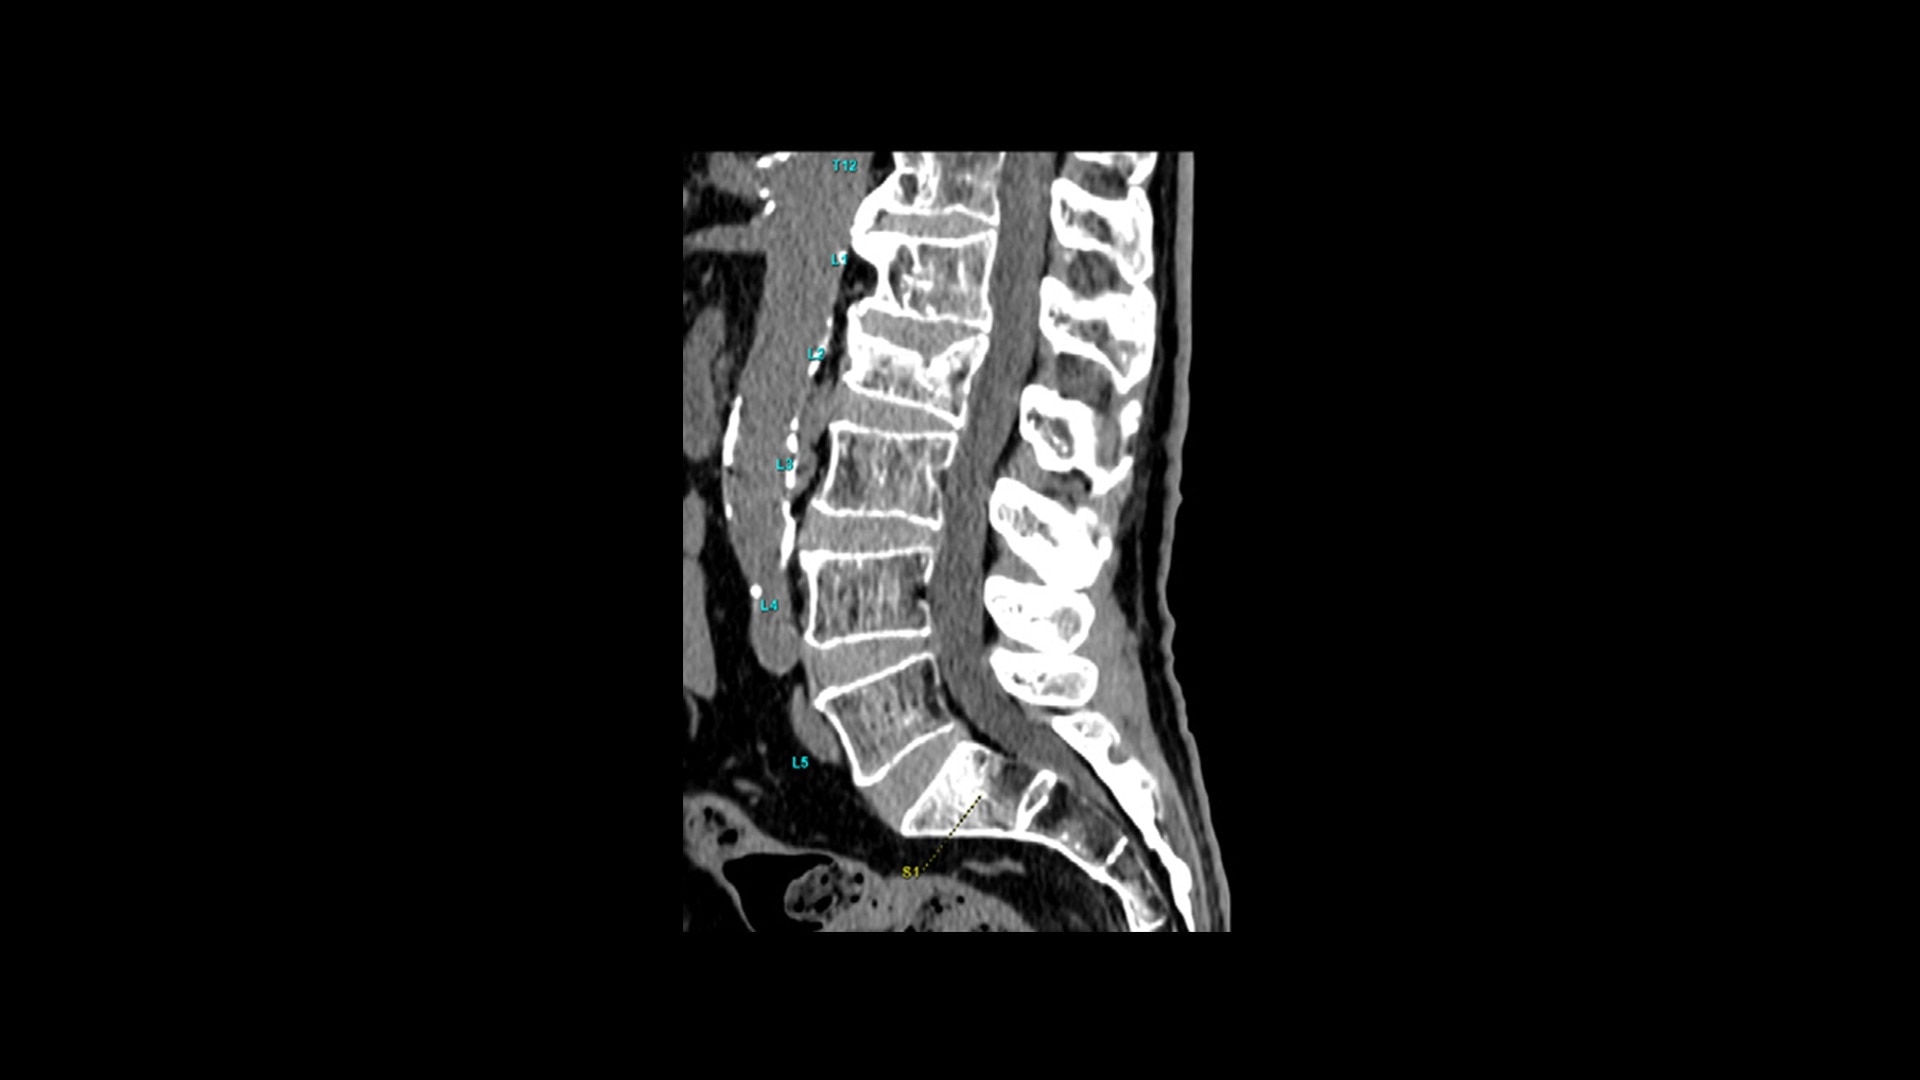

TrueFidelity DL

Deep learning for a deeper understanding

TrueFidelity™ DL is our state-of-the-art image reconstruction technology that uses a DNN to generate high-definition, low-noise CT images. It produces images with exceptional sharpness, low-contrast image quality performance and your preferred noise texture, at the same dose.¹